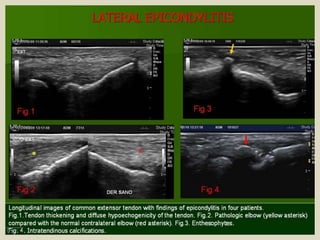

Lateral epicondylitis, also known as “tennis elbow” is an

overuse syndrome of the common extensor tendon. It is thought to

be due to repetitive micro trauma during supination of the forearm

and dorsiflexion of the wrist, that results in the breakdown of fibers

with tissue necrosis and fibrosis. Typically occurs in the 4th and 5th

decades, with equal prevalence in women and men. Patients

complain of poorly defined pain located over the lateral elbow that

is exacerbated with activities requiring wrist extension. Imaging is

reserved for cases which are refractory to conservative treatment,

to exclude other abnormalities and to assess the amount of

damaged tendon before surgery. US findings are: tendon thickening,

diffuse heterogeneity of the tendon with loss of the normal fibrillar

architecture, focal hypoechoic regions, intratendinous calcifications,

adjacent bone irregularity, enthesophytes at the tendon insertion

site, linear intrasubstance tears, peritendinous fluid and thickening

of peritendinous tissues and neovascularity in Colour Doppler